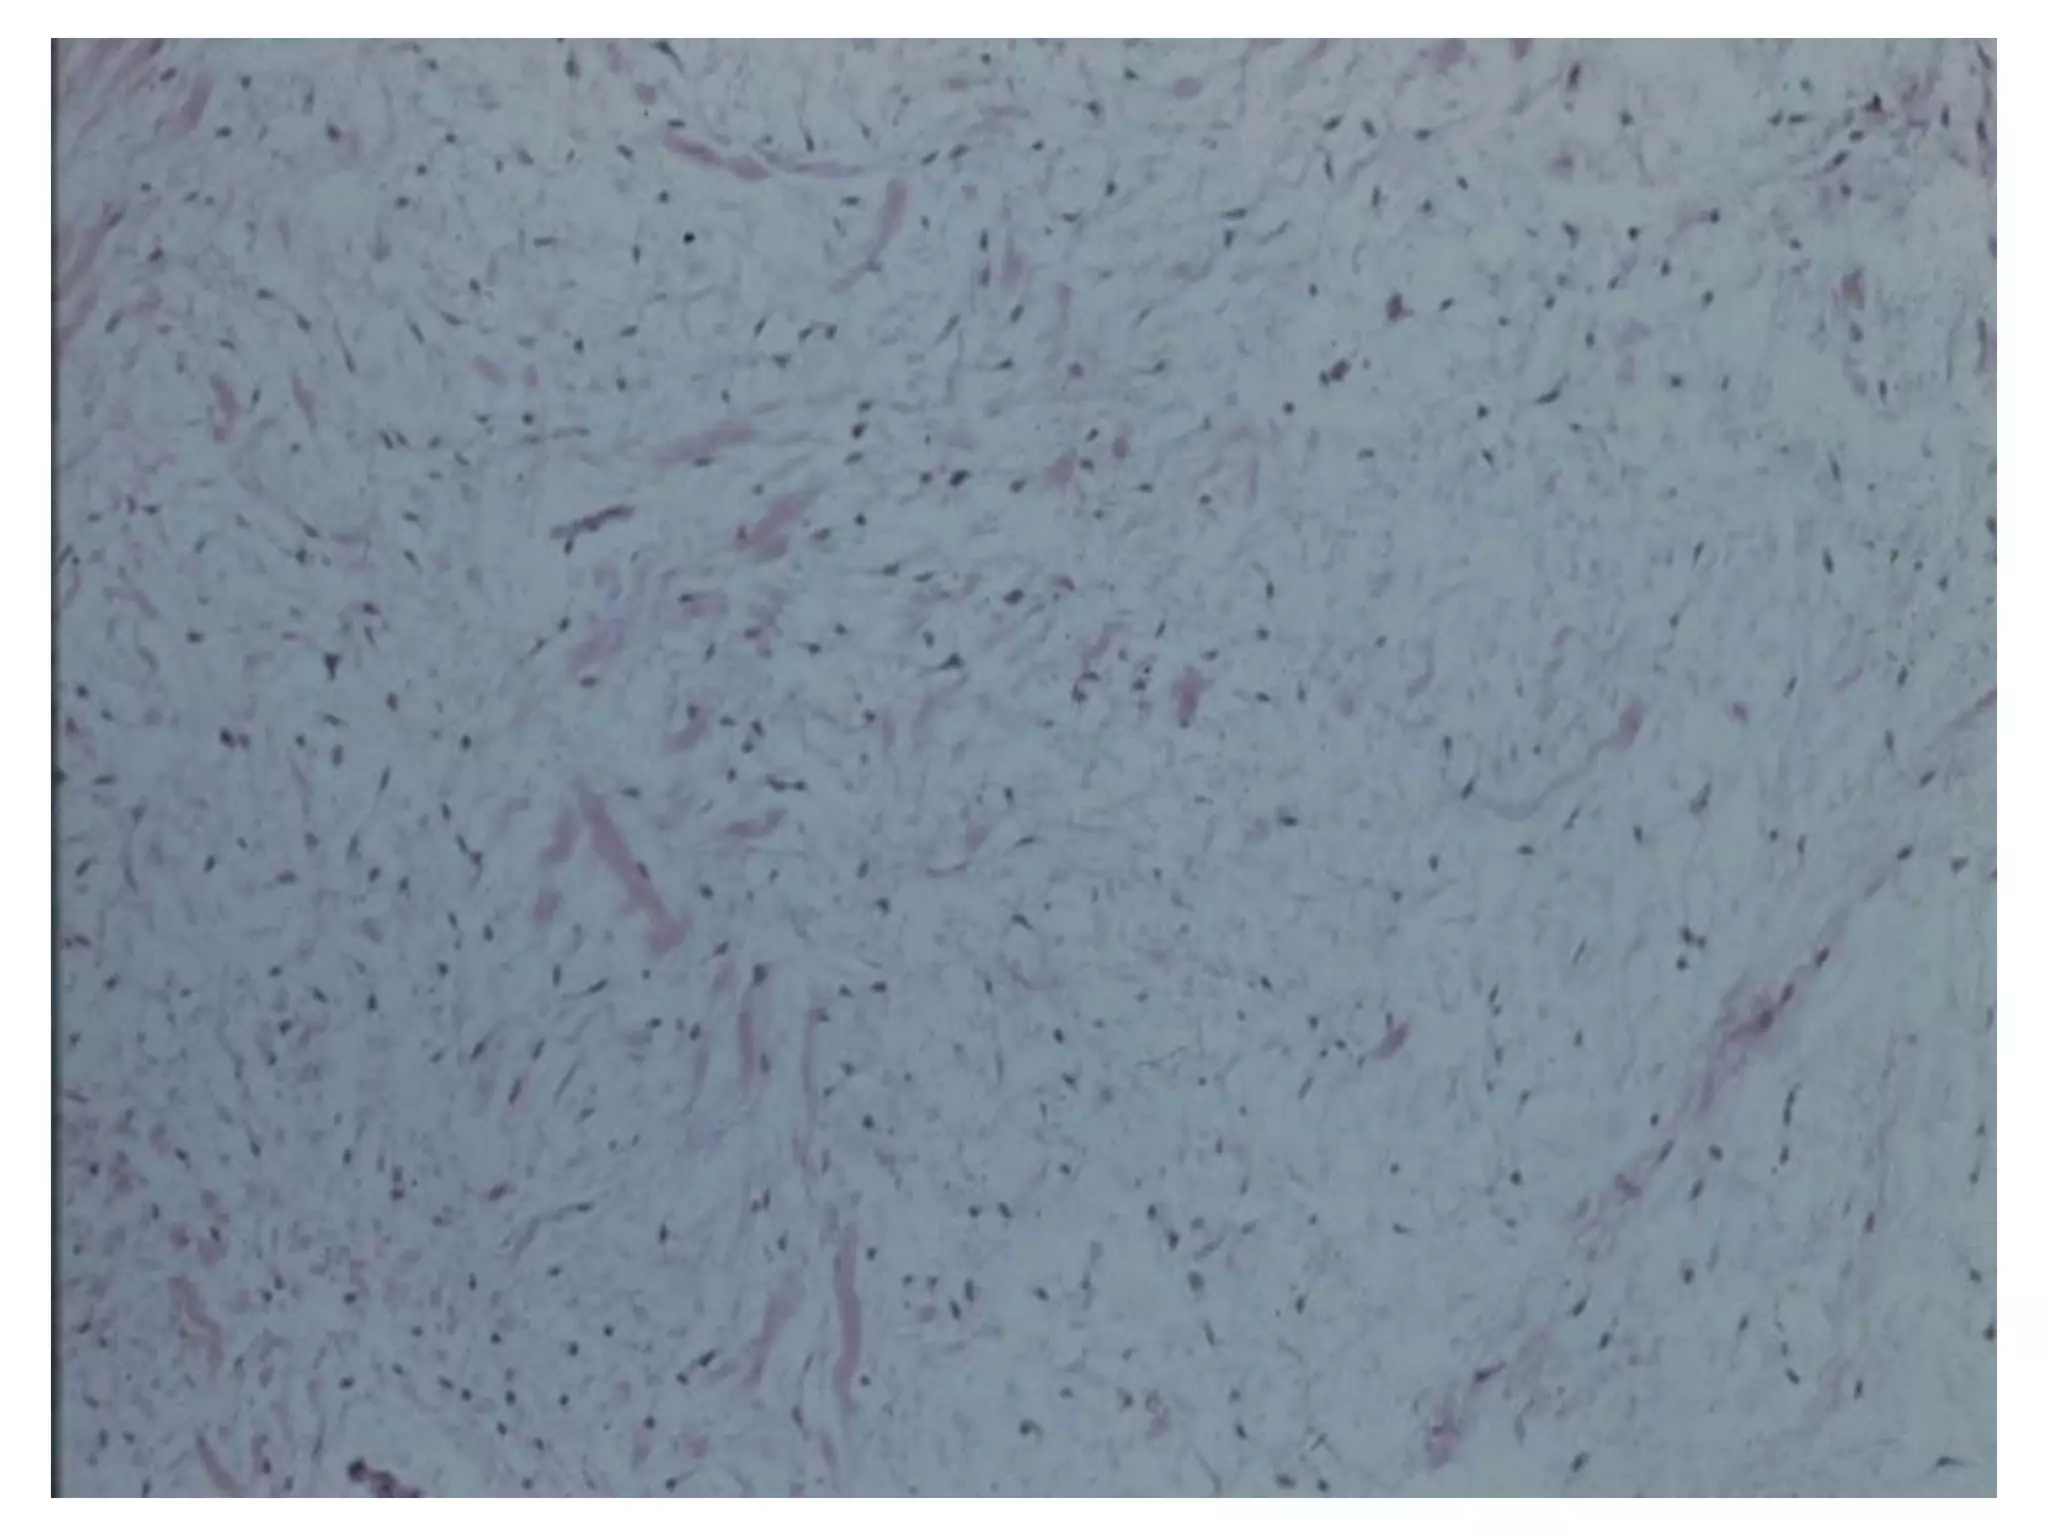

U nhaày do raêng

Giaûi phaãu beänh:

 Goàm caùc teá baøo hình sao, hình thoi vaø hình

troøn naèm rôøi nhau trong moâ ñeäm nhaày loûng

leõo vôùi moät ít boù sôïi collagen.

 Caùc teá baøo bieåu moâ khoâng caàn thieát cho chaån

ñoaùn.

 Coù theå nhaàm vôùi u sôïi nhaày-suïn